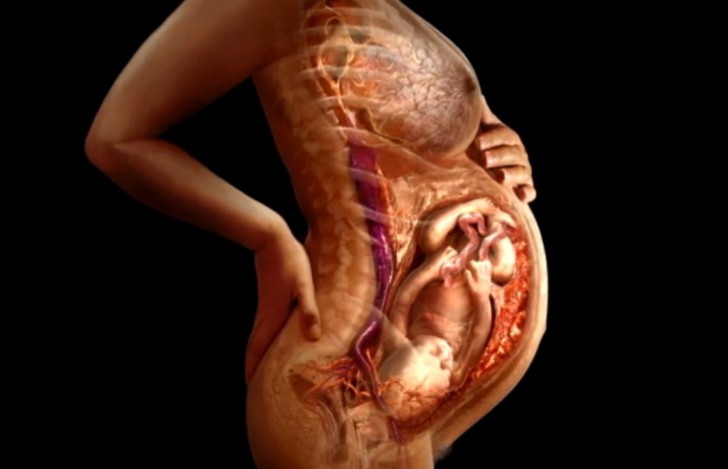

Что такое плацента, какую функцию она выполняет у беременных женщин, что происходит после родов?

Плацента при беременности формируется с момента оплодотворения женщины. Она растет и меняется одновременно с ребенком по мере изменения его потребностей. Плацента при беременности выполняет...